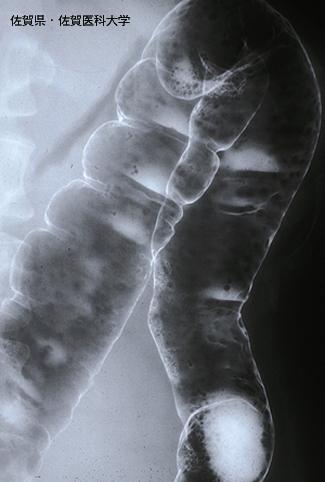

Posted by: Saga Pref., Saga Medical School (Dr.水口)

Criteria of Hist.ClassificationMalignant Lymphoma/Malignant lymphoma

LocationLarge intestine(Colon)/More than one of the above

Technique, MethodX-ray

Size1 - 9

Multiple neoplasm in same organSynchronous